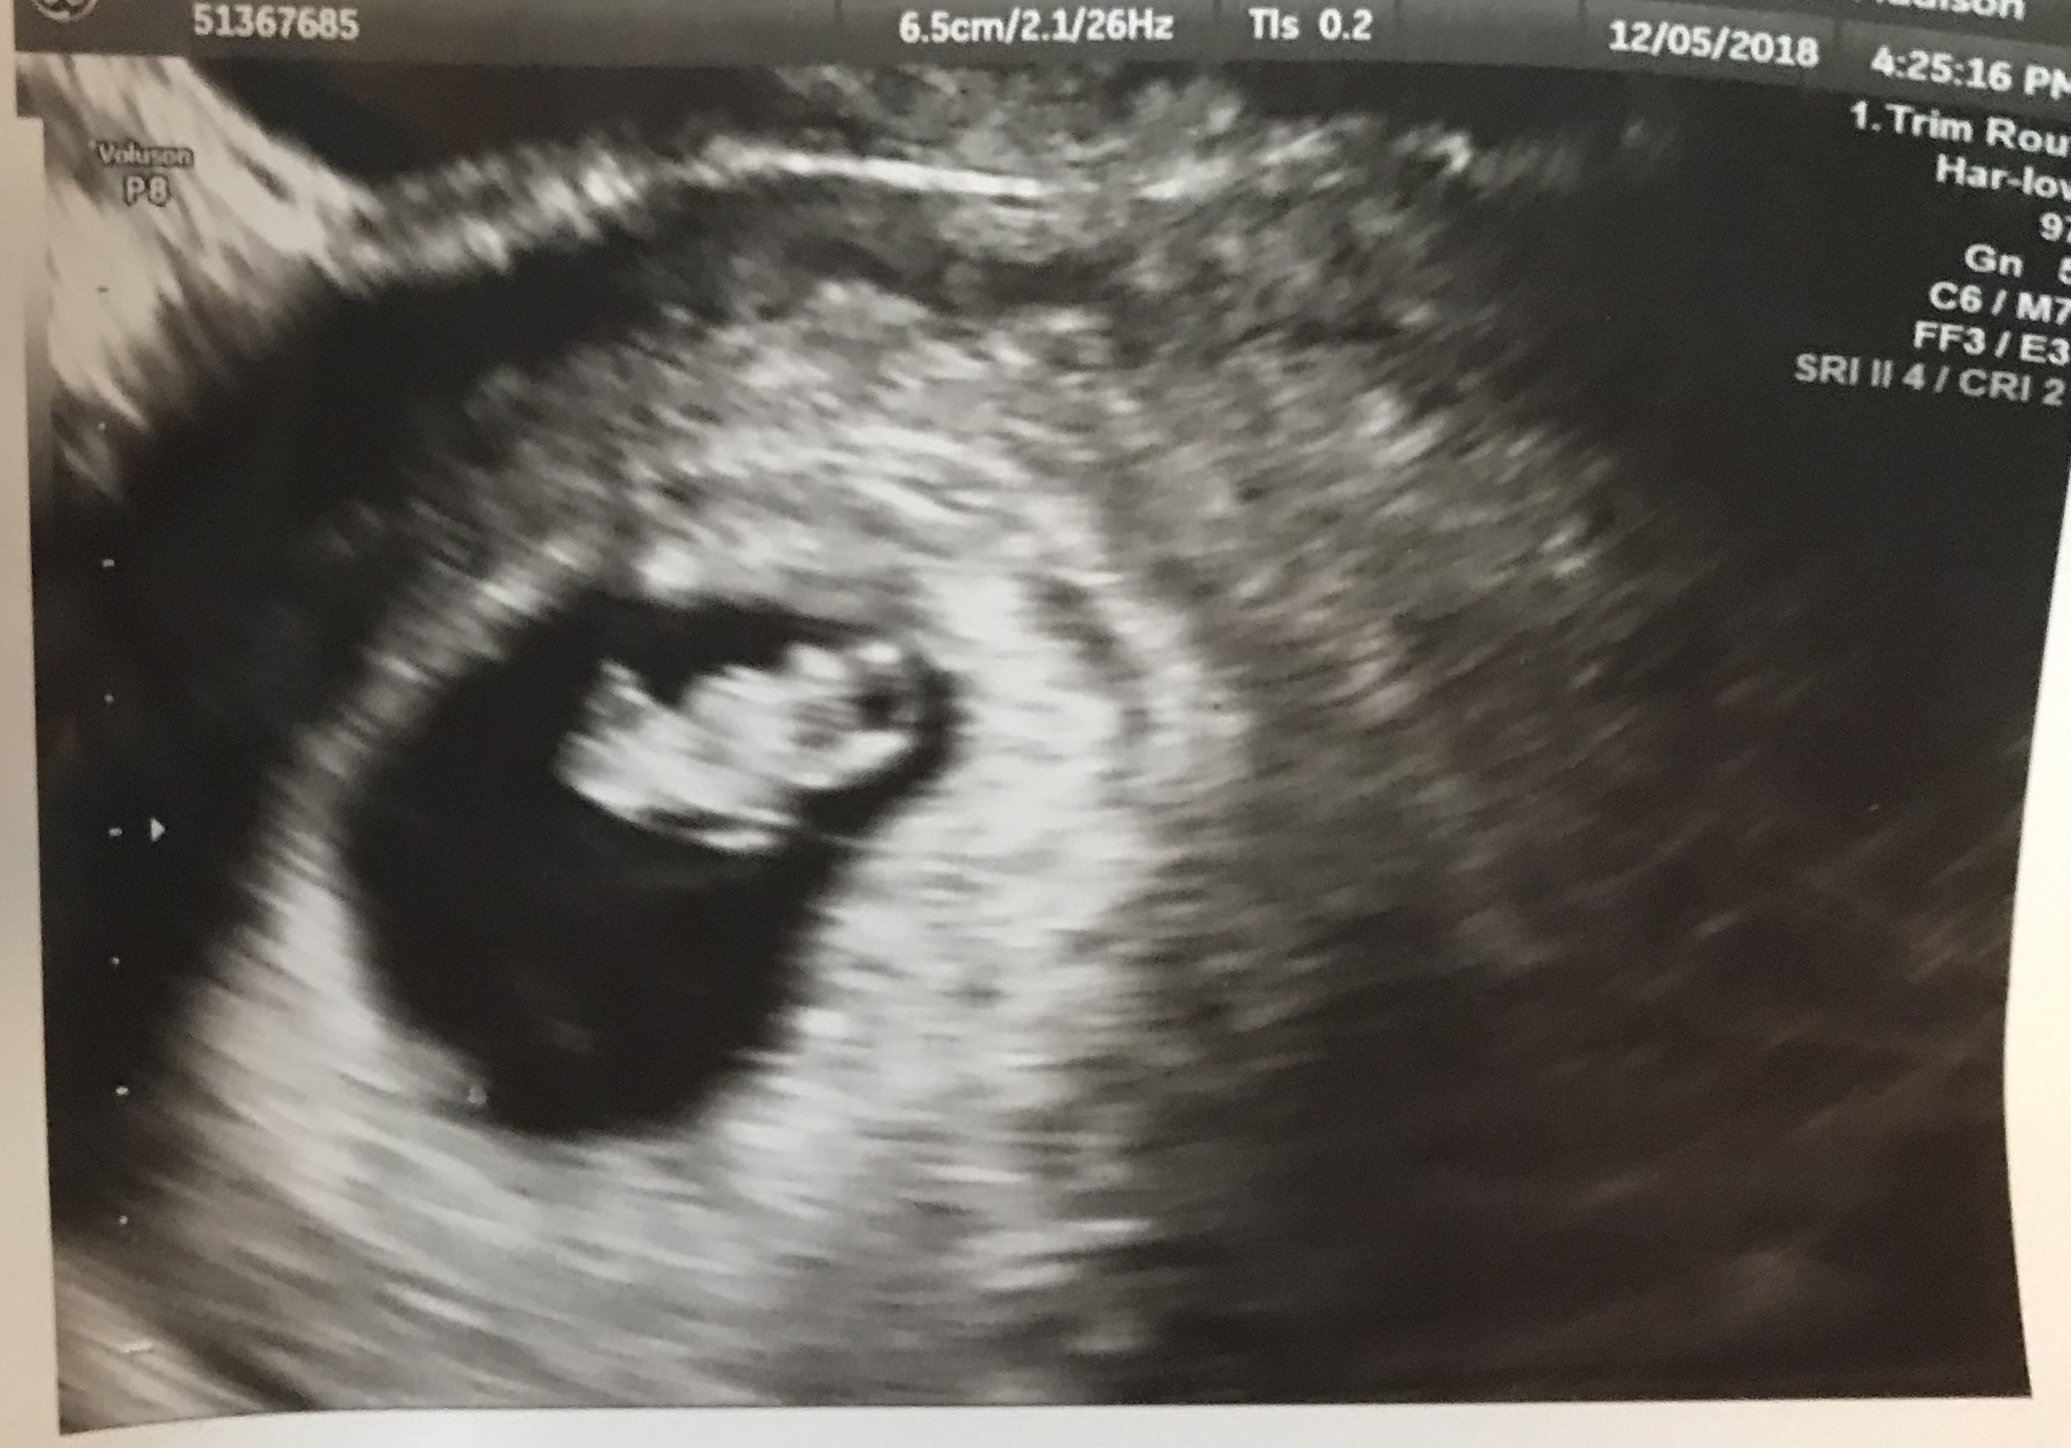

Second ultrasound! I’m 9 weeks today and baby is measuring 8wks 4 days. Within the margin so they’re keeping my 7/11 due date. Strong heartbeat at 178!